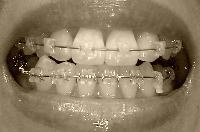

とうとう、全部の歯に装置が付いてから1年になりました!抜歯の隙間も埋まったし、ここまではいろいろあったけどほぼ順調だな~と思います(顔が元に戻ってきたので浮かれているw)もともと、ガタガタを整列させるのに1年、抜歯の隙間を埋めるのに1年、その後微調整で2~3ヶ月という予定だったらしいのです。まあ、微調整が予定以上にけっこうかかりそうではありますが…。先生に「前回歯を削ったけど、どうですか?変わりました?」と聞かれたので「はい、もうかなり劇的に変わったと思います。正直1.5ミリでどれだけ下がるんだろう?と半信半疑だったんですよ~」と答えました。先生はにっこり笑って「それはよかった。実は抜歯しても7ミリぐらいしか隙間は得られないので、1.5ミリっていうのはけっこう大きいんですよ」と言われました。下顎はゴム無しで、針金で固定に入りました。上顎は、アンバランスに大きい右2番(1番と同じぐらい大きい)を3番との隙間で0.5ミリ削って新たに隙間を作りました。そしてパワーチェーンで左右とも3番←→7番を引っ張って前歯を下げる方式。前回と同じです。前からはほとんど変化なくなりましたね。正中はあってないけど、最終的にも合わなくても…あんまり気になりません。そして、横からも撮ってみました比較写真。上の前歯、引っ込んでますよね?もう一息引っ込んでほしいけど、引っ込むってわかったから安心して治療を進められます。たまたま他に患者さんがいなくて、カウンターでちょっと先生と立ち話しました。「今日でちょうど装置が全部ついてから1年なんですよ~」「あ、そうなんですか!抜歯したにしては、やっぱりきたみんさん早いですよ」そして、付け加えて言われました。「お口の中はまだまだお若いってことですよ!」いや~そうですかね~ははは(ノ´∀`*)と笑って帰って来ましたが、そこはかとなく失礼なこと言われた気がする…(^-^;)ちなみに、先生は私より3歳年下なのでした。